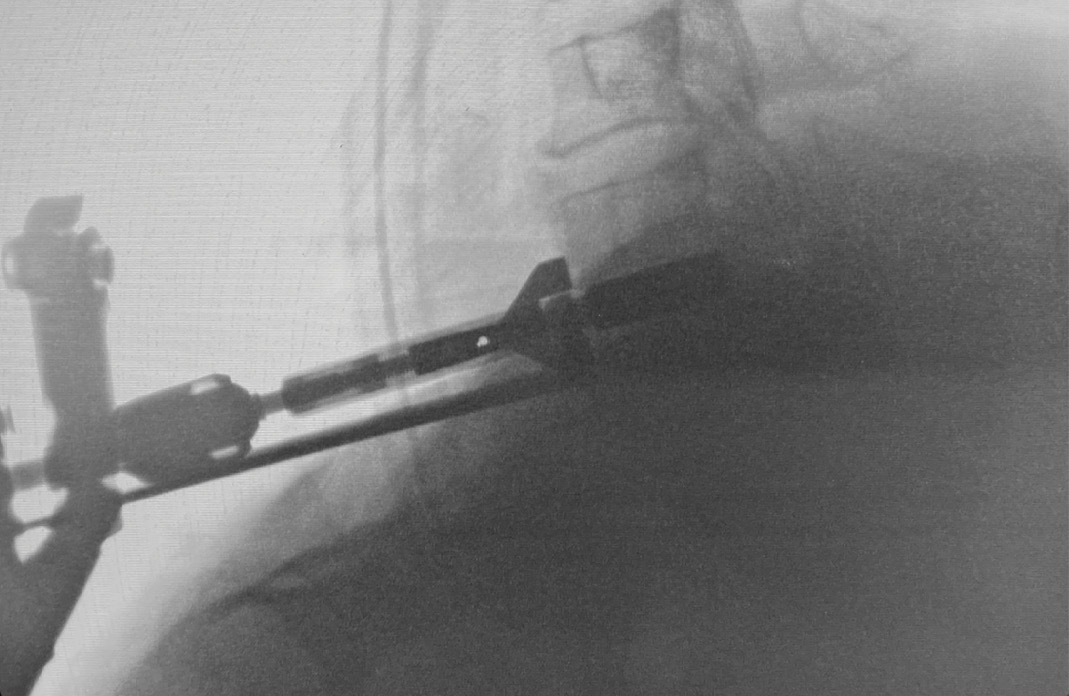

During intra-operative trialing after discectomy and foraminotomies, I felt that the best fit at the C6-7 level was with a prodisc C SK—6mm tall by 18mm deep (Figure 6a). I then performed the discectomy and trialing at the C5-6 level and felt that the prodisc C Vivo was a perfect fit here (Figure 6b).